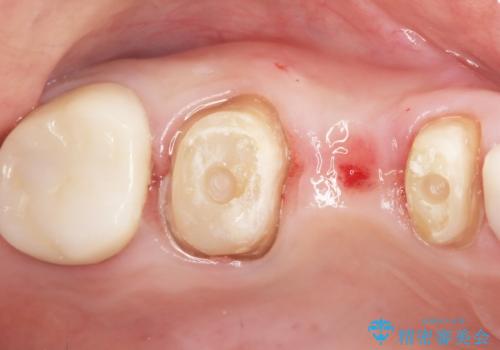

精査したところ、メタルボンドクラウンの金属部分が露出し黒く見えていました。

金属の土台も除去し、ファイバーコア(金属を使わない強度のあるしなやかな土台)へやりかえました。